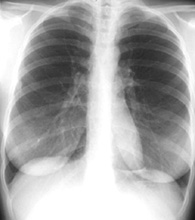

Schema de

radiographie pulmonaire en position debout PA (

postero -anterieure ) . Distance francissable etre

1,2m - 1,4m , rayon central est à horizontale

et situe à T7 . Cliche expose en prise au temps

apnee au cours de phase inspiration |

Les quatres posisions radiographiques de

base du thorax en position AP , PA (

postero-anterieur) , apico lordotique et profile

gauche . La distance trancissable etre 1,2 -

1,4m et le foyer central du rayon en place à T7 ou

au milieu de la ligne de deux bord inferieure de

l'omoplate |

Standard cliche de

radiographie de face ( PA ) et de profile gauche du

poumon .en position debout |